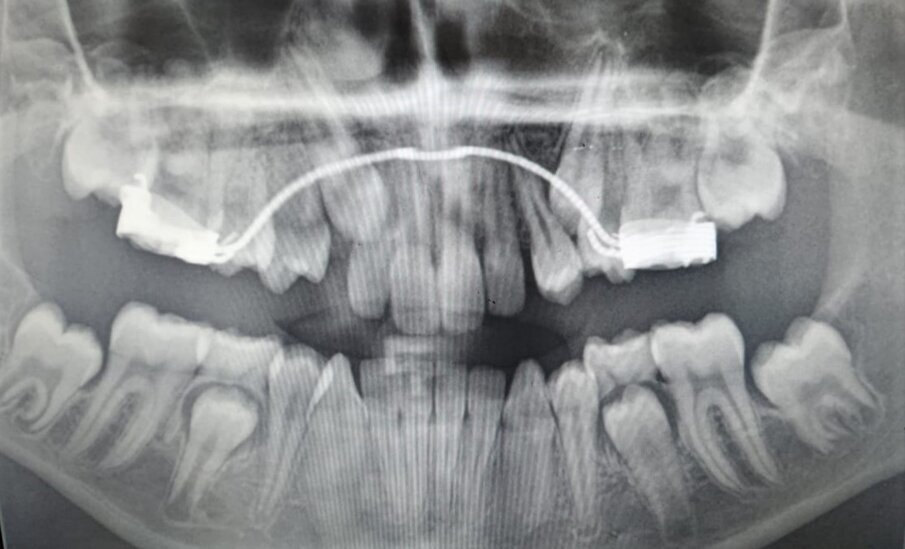

Figg. 2a, 2b: Rx-OPT iniziale di una paziente di anni dieci con trasposizione caninopremolare 1.3-1.4 e ritenzione canina dell’elemento 23(A); Rx-OPT in corso di trattamento della stessa paziente, in cui è mostrata la risoluzione ortodontica con mantenimento dei denti trasposti nel primo quadrante (B).